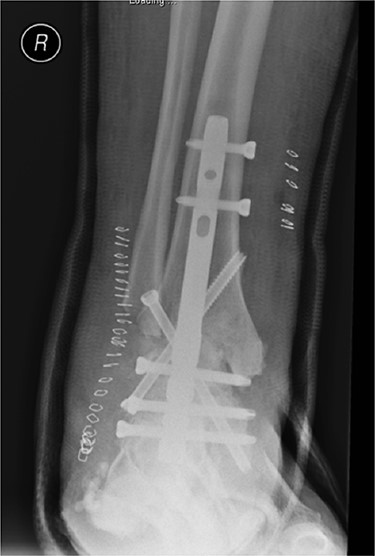

In May 2015, he had a complex midfoot reconstruction, but his foot continued to drift into varus. This was complicated by an infected ulcer on the lateral aspect of midfoot (Fig. 3). Wound infection progressed to osteomyelitis, and in May 2018, he had a hindfoot reconstruction with fusion of tibiotalar and subtalar joints using a Cerament-V-coated hindfoot nail (Figs 4 and 5).

Anterior–posterior radiograph of right ankle demonstrating tibiotalocalcaneal fusion using a hindfoot nail and screws.

Lateral radiograph of right ankle demonstrating tibiotalocalcaneal fusion using a hindfoot nail and screws.